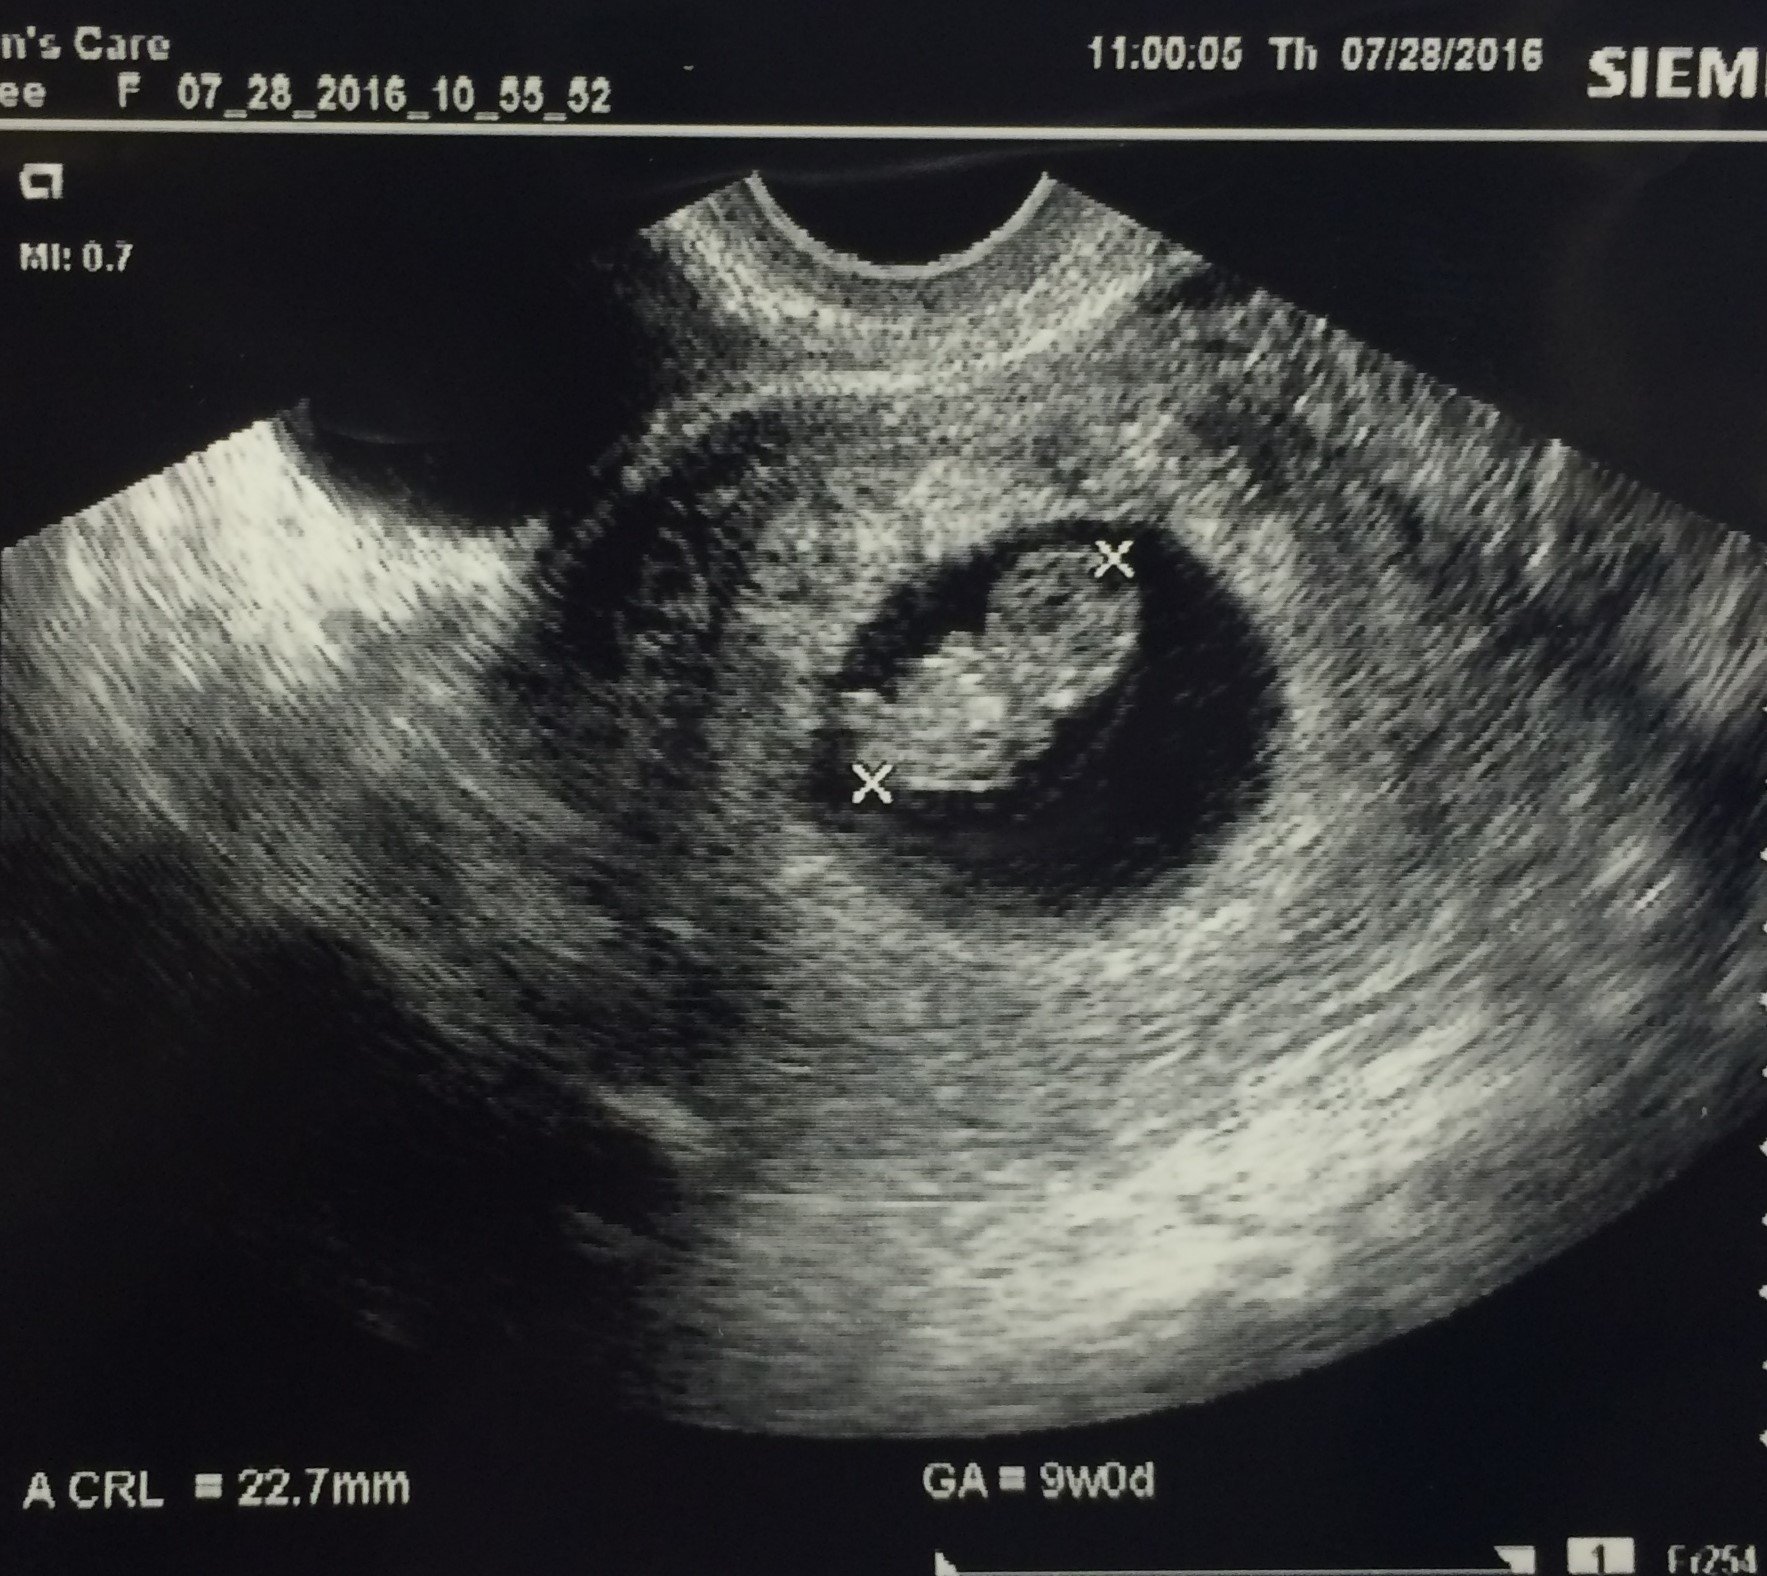

Here is Baby Rick at 8w4d measuring in at 9w0d at our US last Thursday! The little one was swimming around and moving those arms and legs! It was amazing to see as first time parents. Can't wait to see him/her again in a little over 5 weeks